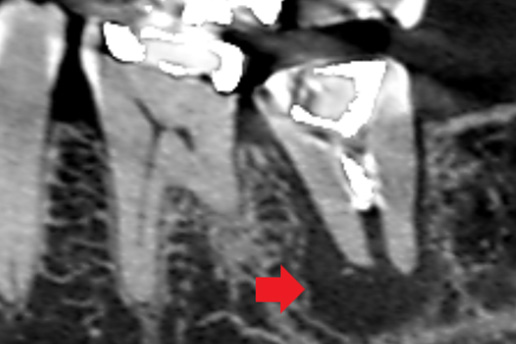

■破折歯

他院で歯が割れているため抜歯と言われたケース。当院で診断したところ破折ではないことが判明し、適切な処置で抜歯せず歯を再生させた。